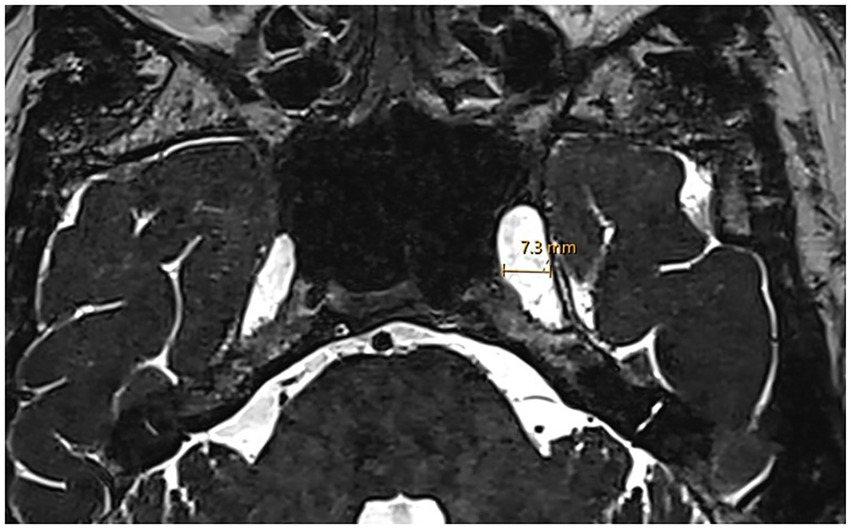

Figure 3

Enlarged Meckel’s cave. Axial 3D T2w SPACE MRI shows an enlarged left Meckel’s cave with a transverse diameter of 7.3 mm.